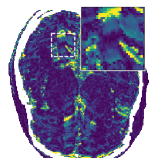

Figure 5 shows an example of a spatio-temporal regularization parameter-map which was estimated using the proposed approach for an acceleration factor of . The network estimates the regularization parameter-map to be pointwise relatively consistenly higher than the spatially required regularization. This result is in fact expected as the temporal dimension is the one for which the gradients of the images are the sparsest because of the high temporal correlation. Further, we see how the network consistently predicts both the spatial regularization as well as the temporal regularization to be less strong in the area where most of the movement is expected, i.e. in the cardiac region.

Figure 6 shows examples of the quantitative (magnitude) images of three of the 112 simulated inversion recovery measurements in the test dataset. We also show the regularization parameter-maps for regularization along the spatial directions and along the inversion-time direction generated by the network. The mean PSNR and SSIM of our proposed method is consistently higher for all considered acceleration factors, even compared to PDHG with regularization strength along spatial and inversion-time direction chosen by grid-search with access to the ground truth images (shown in Figure 8 and Table 2). The resulting parameter-maps after performing the regression on the reconstructed images are shown in Figure 7. Again, our proposed method results in the lowest RMS deviation from the ground truth images (Table 2).